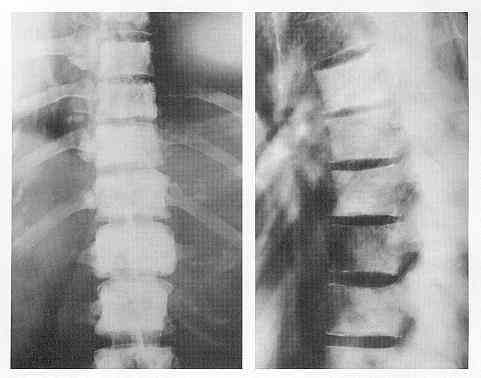

It is easy to over - read an MRI and assume that any abnormal finding is serious. It's worth noting that most older adults have abnormal MRI scans of their back that are entirely benign.

Images of the Spine from Normal Volunteers. (see below)

Herniation of the lumbar disk, as shown in Panel A, is found in 25 to 50 percent of asymptomatic subjects; extrusion of the disk material is found in 1 to 18 percent. Degeneration of the lumbar disk, shown in Panel B, increases with age and is found in 25 to 70 percent of asymptomatic subjects. Signal changes in the vertebral end plates (Panel C, arrows) are found in 10 percent of asymptomatic subjects; severe changes are found less frequently. Panel D shows a disk with a bright signal in the annular fissure. This represents degenerative changes that are found in 14 to 33 percent of asymptomatic subjects. Despite the high prevalence in healthy persons, these findings are often described as causing serious low back pain and are treated with spinal fusion.